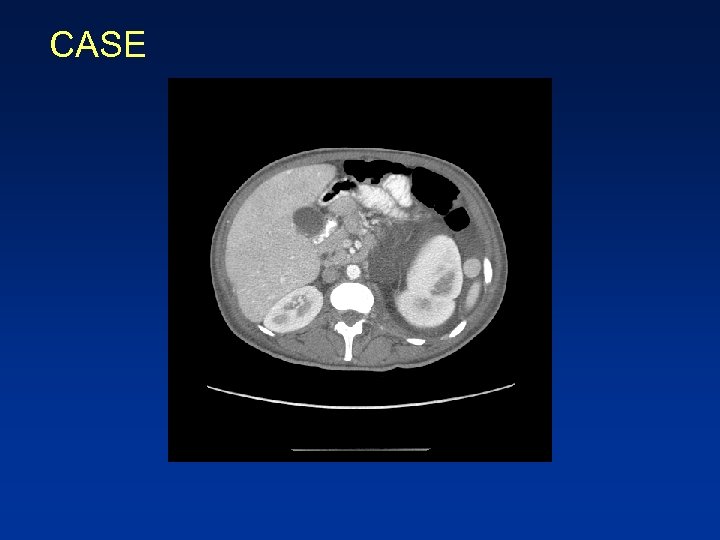

CASE